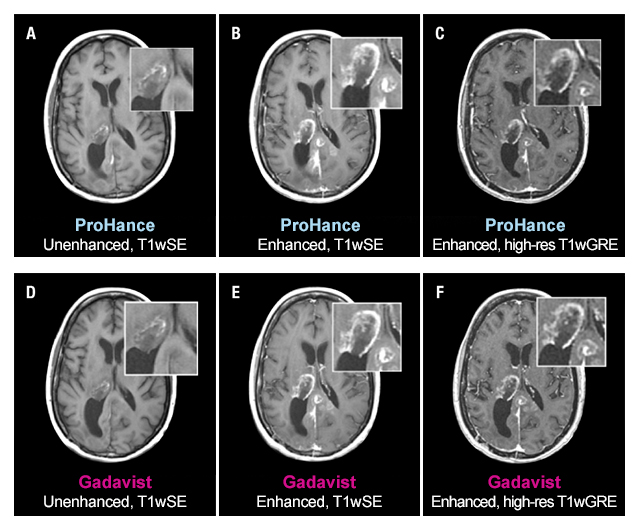

Case Study 2

51-year-old female with glioblastoma multiforme. Rim-enhancing mass in right thalamus with extension into the posterior interhemispheric region is clearly seen in both examinations. No differences in contrast enhancement or in the morphology of lesions are apparent.1

The TRUTH study results demonstrate no differences in contrast enhancement of lesion morphology.1

The 95% confidence intervals for all qualitative assessments confirm that ProHance is not inferior to Gadavist.1

No significant differences noted by any reader for any parameter:1

- Global Diagnostic Preference

- Lesion Border Delineation

- Lesion Internal Morphology

- Lesion Qualitative Contrast Enhancement

- Lesion Extent